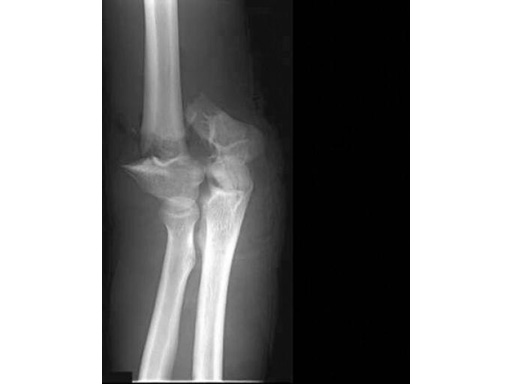

40-year-old man, 13-C3 fracture treated with DHP.